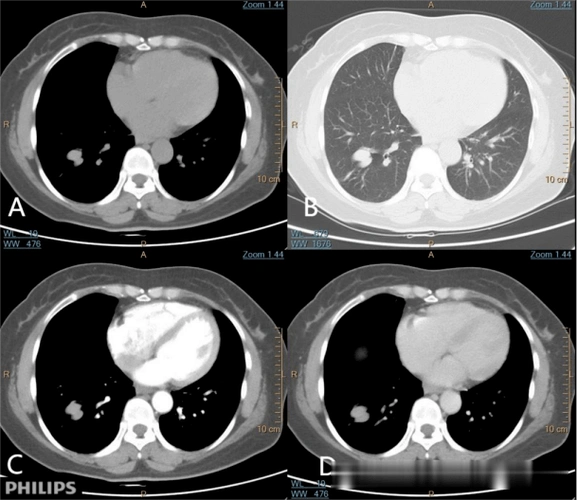

pet ct=真相!_病变_玻璃_显示